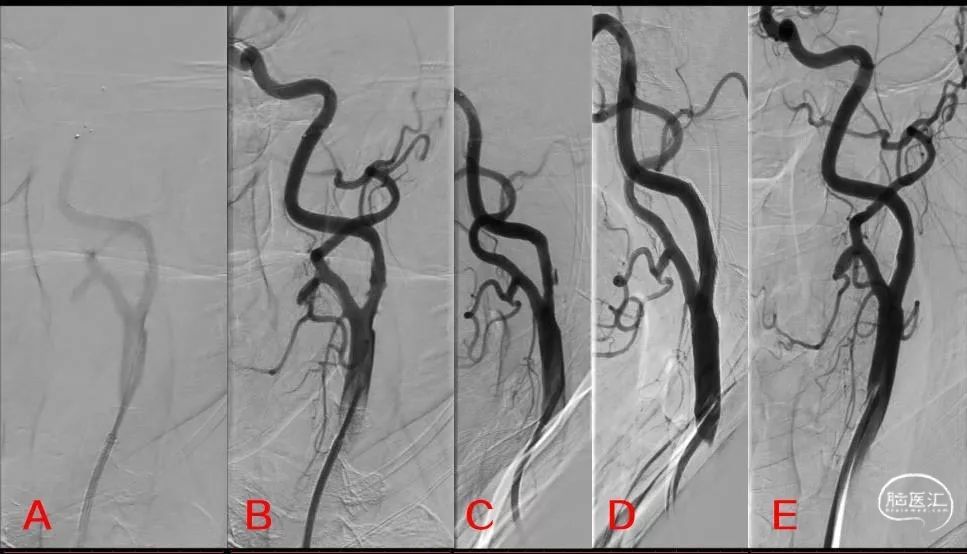

在脑梗死发病的第5天(NIHSS 3分),患者进行了全脑血管造影,提示左侧颈内动脉起始部中度狭窄伴血栓形成,同侧颈内动脉远段、大脑中动脉显影良好(图1)。

图1:左侧颈动脉造影

将栓子保护装置(EV3-SPIDER 5mm)在颈动脉岩骨段释放,球囊(AVIATOR 5×30mm)以14个大气压的压力进行预扩张,残余轻度狭窄,伴夹层形成,查体患者无不适,语言功能、肢体活动正常,同术前。因颈内/颈总动脉直径相差较大,植入锥形开环支架(ACCULINK 6-8×40mm),术后造影左侧颈动脉血管成形良好,同侧颅内血管造影无异常(图2)。

图2:A:显示保护伞位置,B、C:球囊扩张后,D、E:支架植入后